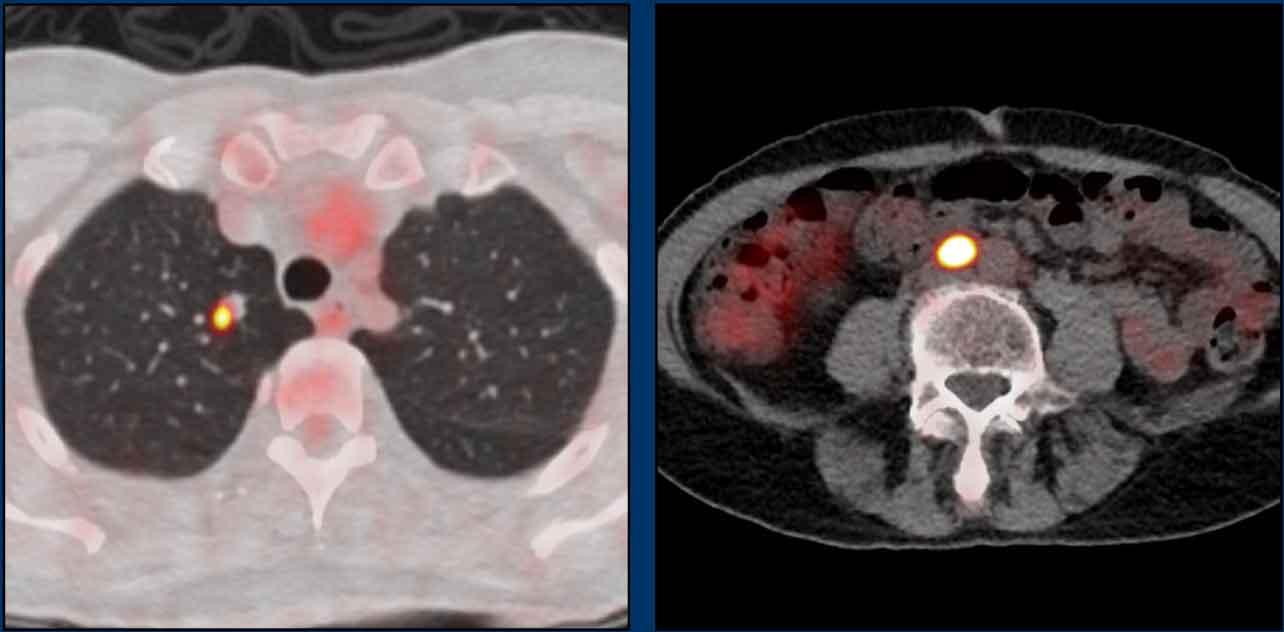

Giai đoạn M

Khoảng 6% bệnh nhân ung thư hậu môn có di căn xa tại thời điểm chẩn đoán (3,4).

Di căn xa làm giảm nặng nề tiên lượng với tỷ lệ sống còn toàn bộ trung bình 5 năm chỉ đạt 10-20%.

Các vị trí di căn xa phổ biến nhất là các hạch bạch huyết xa như hạch chậu chung, hạch cạnh động mạch chủ và hạch trên cơ hoành, tiếp theo là di căn gan và phổi.

Phương thức phân giai đoạn được khuyến nghị cho giai đoạn M trong ung thư hậu môn là FDG-PET vì hầu hết ung thư hậu môn đều là ung thư biểu mô tế bào vảy, có tăng hấp thu FDG chuyển hóa rõ rệt trên PET.

Thay thế, có thể thực hiện CT pha tĩnh mạch cửa vùng ngực và bụng.

Hình ảnh

Hai tổn thương di căn xa bắt FDG rõ rệt trên PET: một nốt nghi ngờ ở phổi phải và một hạch bạch huyết cạnh động mạch chủ xa.